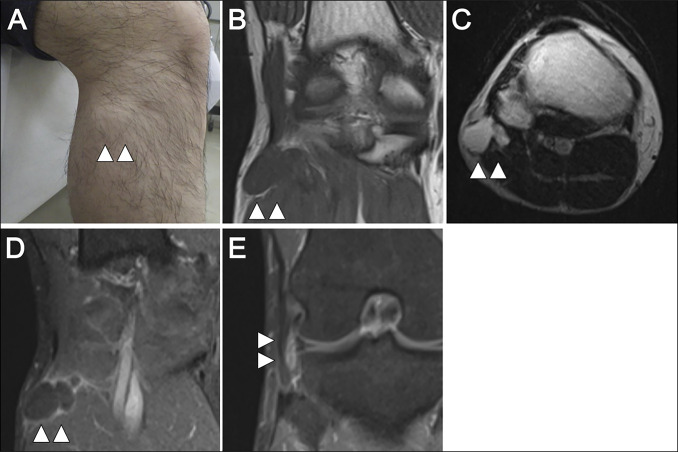

Common peroneal nerve palsy is often caused by compression at the fibular head, with ganglion cysts being the most common etiology. Although rare, meniscal cysts can also compress the nerve. We report a case of common peroneal nerve palsy due to a lateral meniscal cyst, successfully treated with surgery. A 38-year-old man presented with progressive pain and numbness in the right lateral knee and foot, along with difficulty dorsiflexing the ankle without any apparent history of trauma. Examination revealed a palpable mass on the lateral knee and sensory deficits in the superficial peroneal nerve distribution. Magnetic resonance imaging demonstrated a cystic lesion originating from the lateral meniscus. Nerve conduction studies showed reduced conduction velocity, confirming a diagnosis of common peroneal nerve palsy secondary to a lateral meniscal cyst. The patient underwent surgical excision of the cyst and arthroscopic meniscal repair. Intraoperatively, the cyst was compressing the common peroneal nerve. Postoperatively, motor function recovered over 1 year, with minor residual sensory deficits. No recurrence was observed at 1-year follow-up. Lateral meniscal cysts are a rare cause of common peroneal nerve palsy. Early diagnosis and surgical intervention can prevent permanent nerve damage and ensure functional recovery.